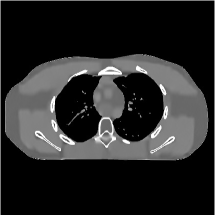

We firstly hand-tuned the reconstruction parameters () for one test slice and treated this set of parameters as the baseline. Similar to the PWLS-EP algorithm, we could determine the optimal (in terms of optimal RMSE) parameters for other testing slices by tuning the base parameters in a small range. However, we found that the change in reconstruction quality by picking a common set of parameters instead of slice-wise optimized parameters is quite small (only 0.2 HU in RMSE and without the loss of details). Therefore, the same set of parameters (baseline parameters) were used across testing cases and shown to be effective over the cases. In particular, we selected slice 48 of the XCAT phantom as the case for parameter tuning and set the regularization parameters (after tuning over ranges of values) as , , for ST, , , , , for MARS2, , , , , , , for MARS3, , , , , , , , , , , for MARS5, and , , , , , , , , , , , , , , for MARS7, respectively. In Fig. 14 in the supplement, we give the reconstructions for slice 48 of the XCAT phantom with various methods. Figs. 4 and 5 here show the reconstructions for two independent test cases (slice 20 and 60 of the XCAT phantom). Both of them used the same set of parameters obtained for slice 48. The zoom-in regions give an explicit comparison between the multi-layer sparsifying transform models and other methods such as FBP, PWLS-EP, and PWLS-ST. PWLS-MARS achieves better noise reduction and higher contrast.

III.C. Low-dose Experiments with Mayo Clinic Data